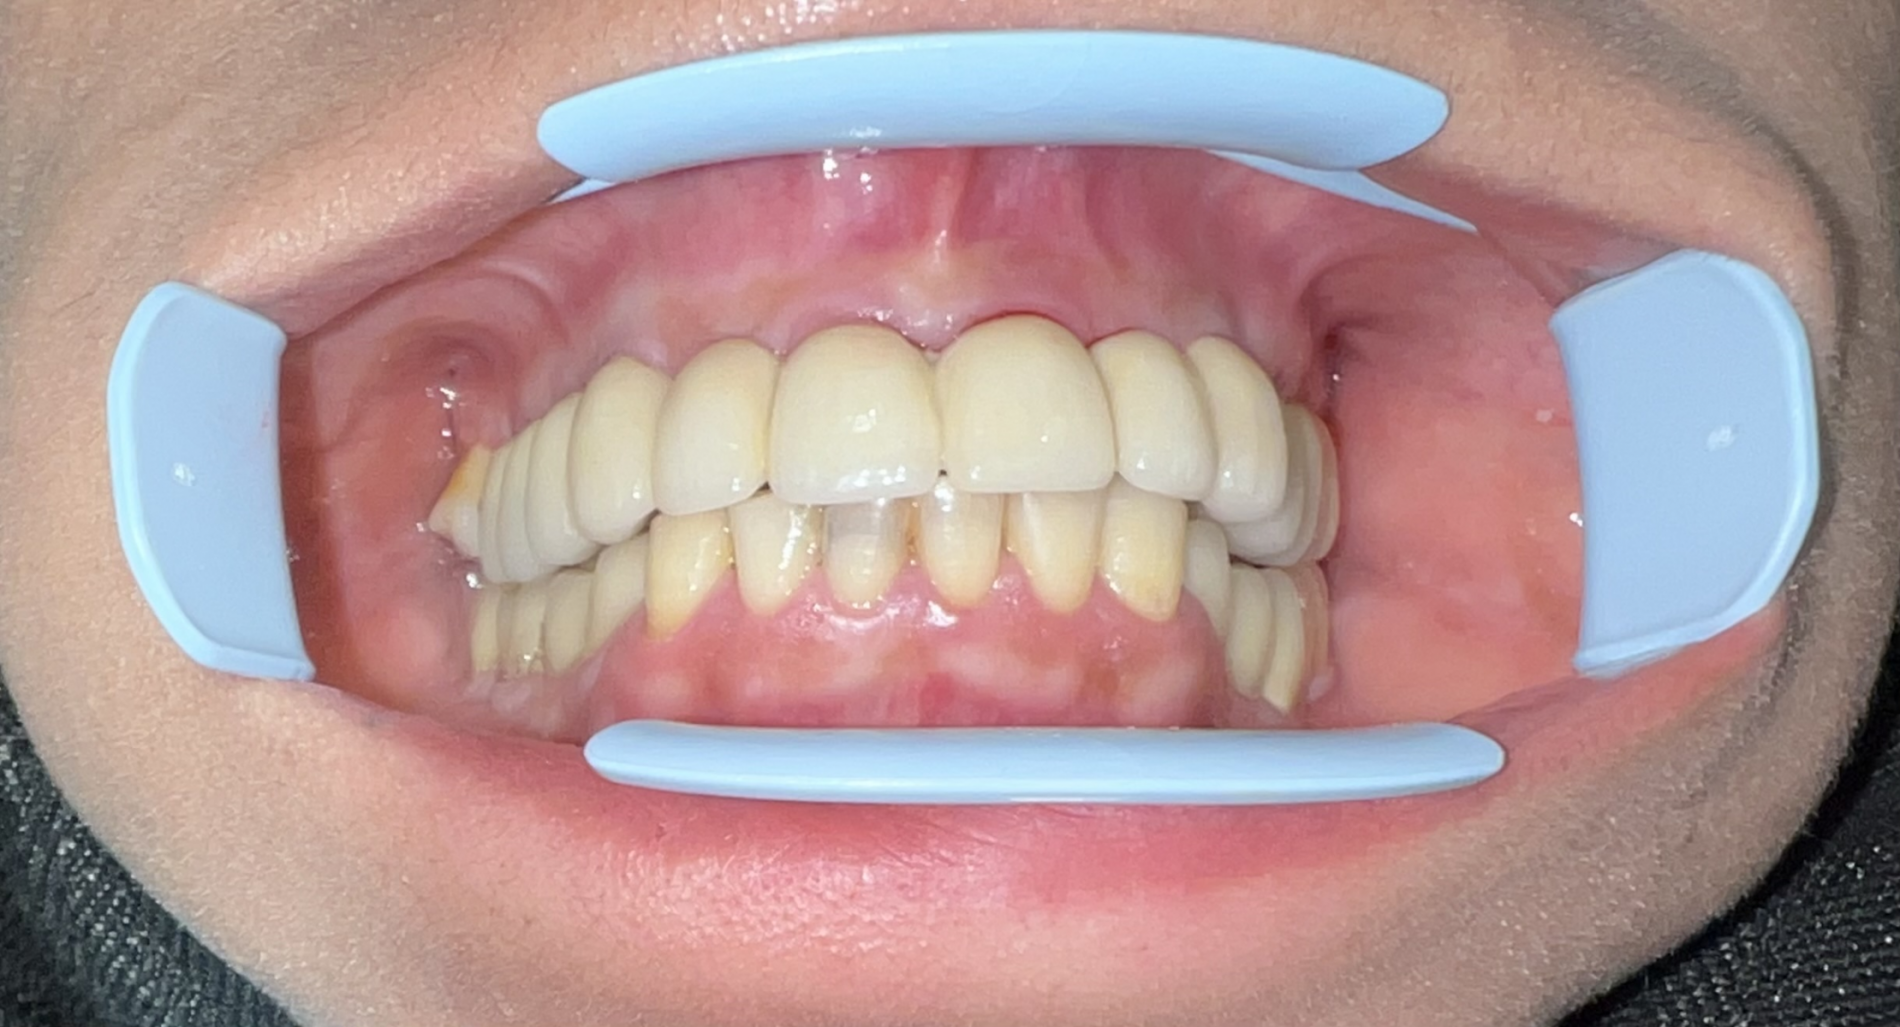

کشیدن دندانهای پوسیده و همزمان ایمپلنت

در آوردن روکشها,کشیدن دندانهای پوسیده و کاشت ایمپلنت اشترومن و پیوند استخوان در یک جلسه.